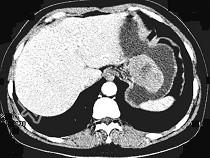

- 单项选择题女,51岁, 上腹部隐痛不适,CT检查如图, 可能的诊断是  (    )

- A、胃癌

- B、胃息肉

- C、胃腺瘤

- D、胃溃疡

- E、胃间质瘤